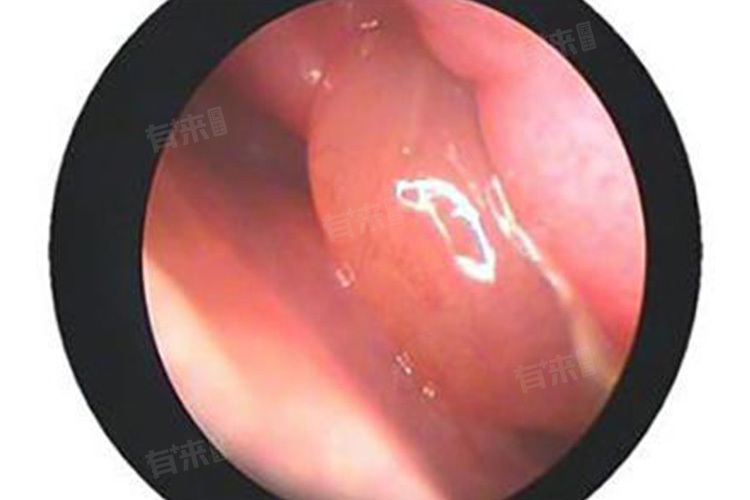

- 当发现鼻子内部有肉凸起时,需进行一系列检查以明确病因,首先是前鼻镜检查,医生通过前鼻镜撑开鼻孔,直接观察鼻腔前部情况,查看肉凸起的位置、大小、颜色、形态等,初步判断其性质,若肉凸起位于鼻腔深部,前鼻镜无法看清全貌,则需进一步检查。

- 鼻内镜检查是重要手段,能深入鼻腔各个角落,更清晰地观察肉凸起及其周围组织,可发现微小病变,并能在直视下取组织进行病理活检,对明确诊断至关重要,通过病理检查可判断是良性病变还是恶性肿瘤。影像学检查也不可或缺,如鼻部CT扫描,能清晰显示鼻腔及鼻窦的解剖结构,了解肉凸起的范围、与周围组织的关系,对于判断肿瘤是否侵犯周围骨质等具有重要意义;MRI检查则对软组织分辨力高,有助于进一步明确病变性质,特别是在判断肿瘤的侵犯程度和范围方面有独特优势。